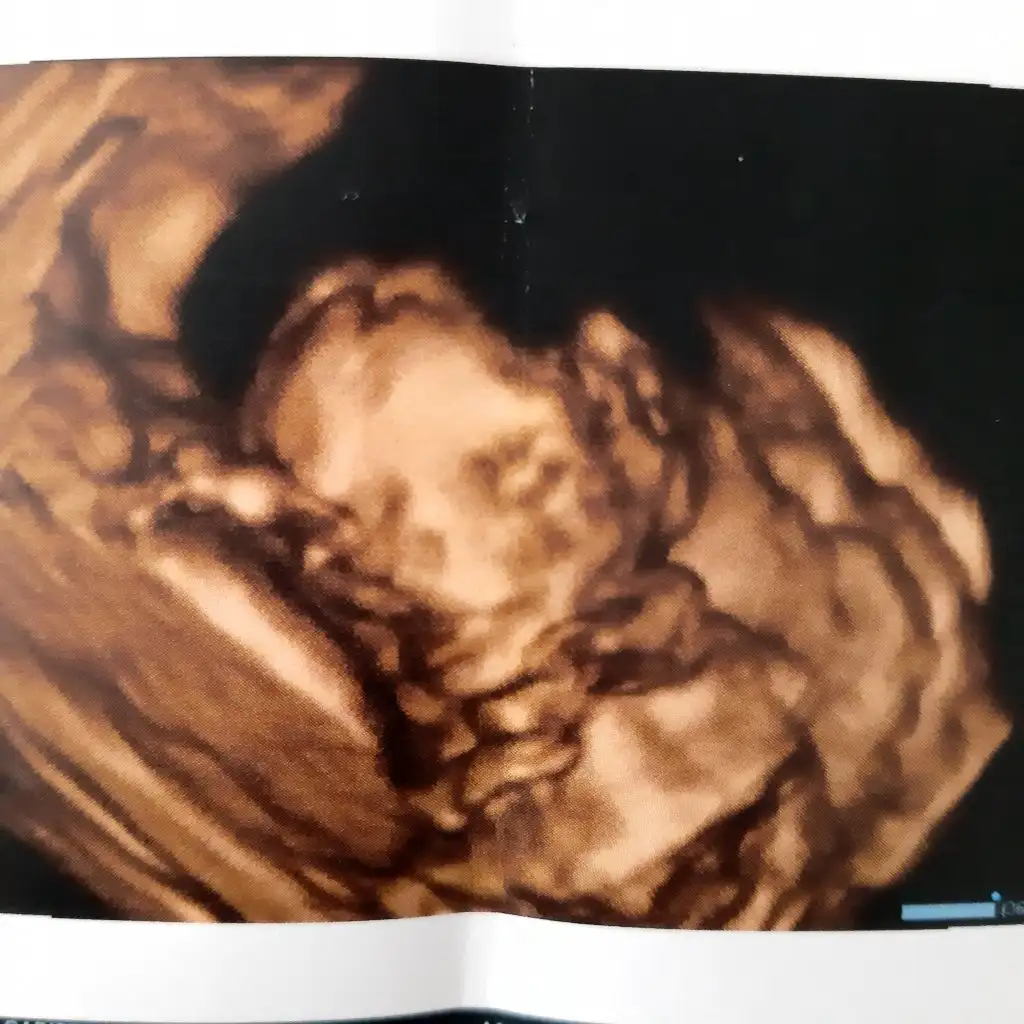

Minik burunlu

Köfte dudaklı bir kız

Yaaaa çok güzelUyuyordu .tofıta atmıştım ağzına ama.geç yattım gece

maşallah ne güzel , demekki hissettirmeden coşuyor içerde bebiş:)))Selammm